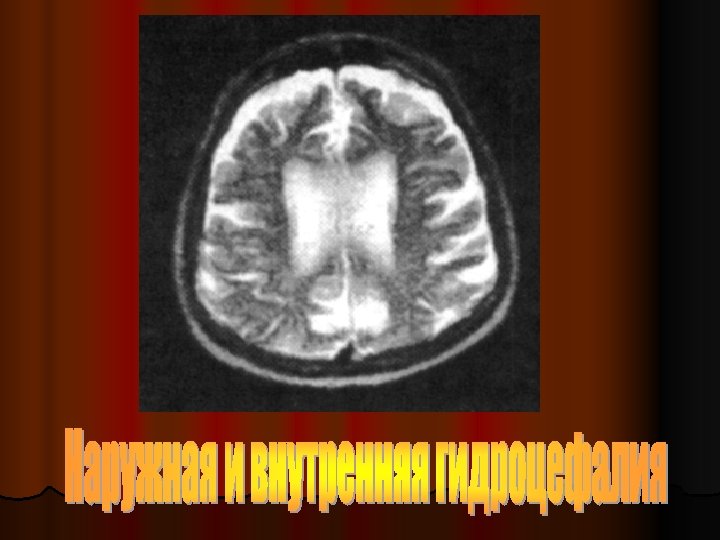

Патоморфология ХГЭ l Лейкоареоз (мелкоочаговые и диффузные изменения белого вещества субкортикально) l Лакунарные инфаркты (очаги ишемии в виде полости 0, 1 -1, 5 см) l Лакунарное состояние

МРТ при ХГЭ Перивентрикулярные диффузные изменения у больного 56 лет с тяжелой АГ (“гипертоническая лейкоэнцефалопатия” – лейкоареоз)